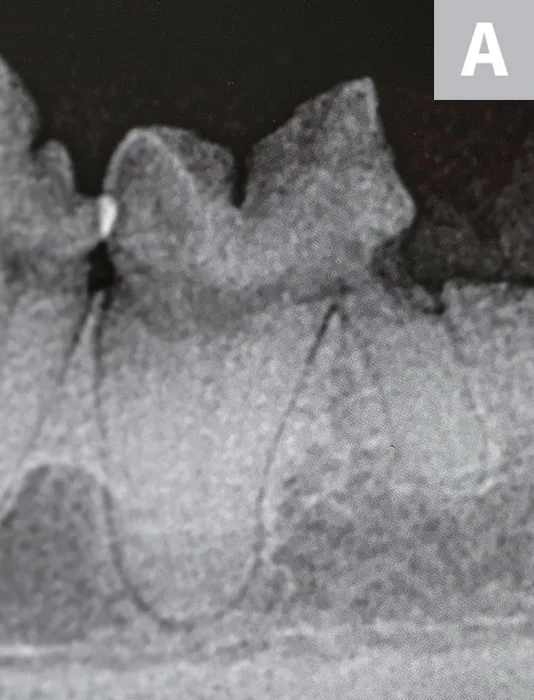

Tooth resorption type is determined via intraoral radiography based on root opacity and periodontal ligament space (see Types of Tooth Resorption Based on Radiographic Appearance and Figure 2).

Radiograph of a left mandibular molar tooth in a cat with Type 1 resorption (A) in which focal or multifocal radiolucency can be seen with otherwise normal radiopacity and normal periodontal ligament space. Radiograph of mandibular incisors and canine teeth in a cat with Type 2 resorption (B; white arrow) in which narrowing or disappearance of periodontal ligament space is present in at least some areas, and part of the tooth demonstrates decreased radiopacity. Radiograph of the right maxillary third and fourth premolars in a cat with Type 3 resorption (C); the third premolar features Type 1 resorption of the mesial root (arrowhead) and Type 2 resorption of the distal root (dashed arrow) with exposure to the oral cavity.